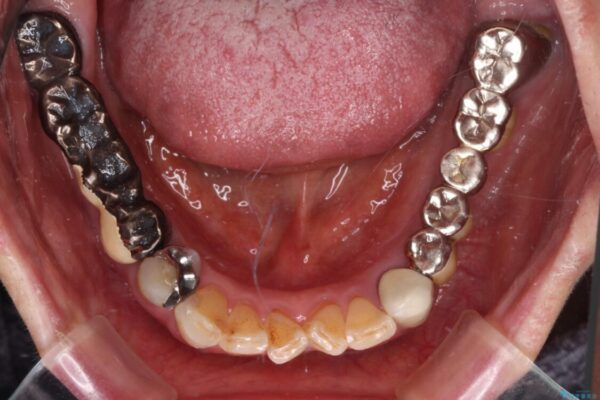

処置を予定していた歯を仮歯に変えた時点で、下顎前歯の部分矯正を行うかどうかを尋ねたところ、折角なので行いたいと言うことでしたので、矯正治療を行うこととしました。

治療途中